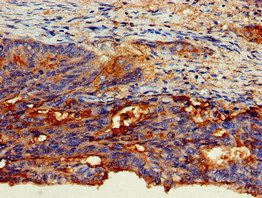

Immunohistochemistry of paraffin-embedded human colon cancer using CSB-PA005166LA01HU at dilution of 1:100